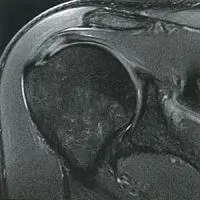

В современной медицине первенство в диагностики импинджмент–синдрома занимают магнитно-резонансная томография (МРТ) плечевых суставов и ультразвуковое исследование (УЗИ) плечевых суставов. При этом появилась возможность определить степень выраженности патологии, диагностировать начальные симптомы заболевания, своевременно провести профилактическое лечение и избежать оперативного лечения, в котором нуждаются пациенты на поздних стадиях заболевания.